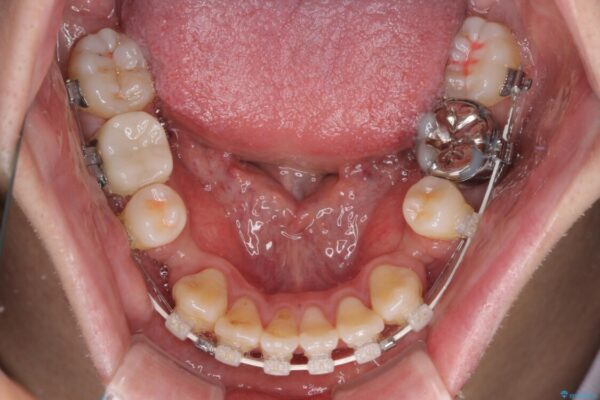

治療途中

• 口元の突出感を改善!目立ちにくいワイヤー矯正で自信を持てる自然な横顔に 治療途中画像